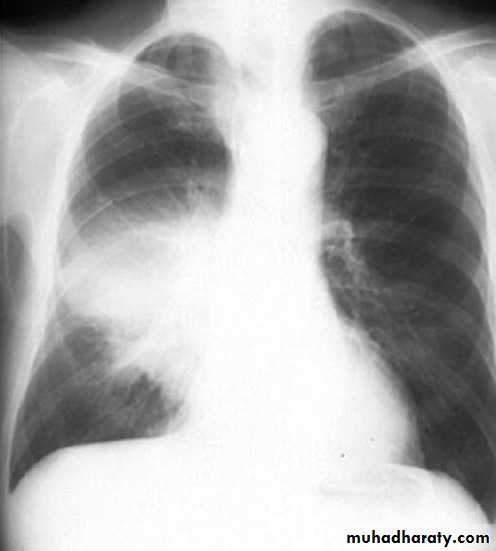

Pleural effusion ( free)

Massive pleural effusion